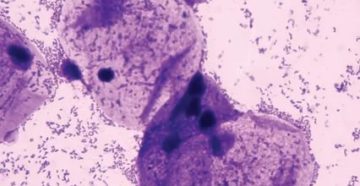

Что такое коккобациллярная флора в мазке В лабораторной диагностике применяется классификация микроорганизмов, которые можно обнаружить…